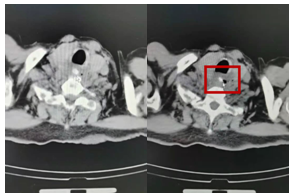

入院后,完善术前检查后,评估老人身体情况,于今日在北大人民医院张立红主任的指导下,麻醉科医生、手术室护士的配合下,科内人员协同下,徐景利主任主刀,顺利完成了我院首例全麻下食管镜下食道异物取出术,术后,患者咽喉部梗阻感、疼痛感、压榨感消失,呼吸平稳,吞咽功能恢复。患者脸上洋溢着笑容,家属连声表示感谢,是对医院服务品质的认可,也是对医务人员工作的充分肯定。